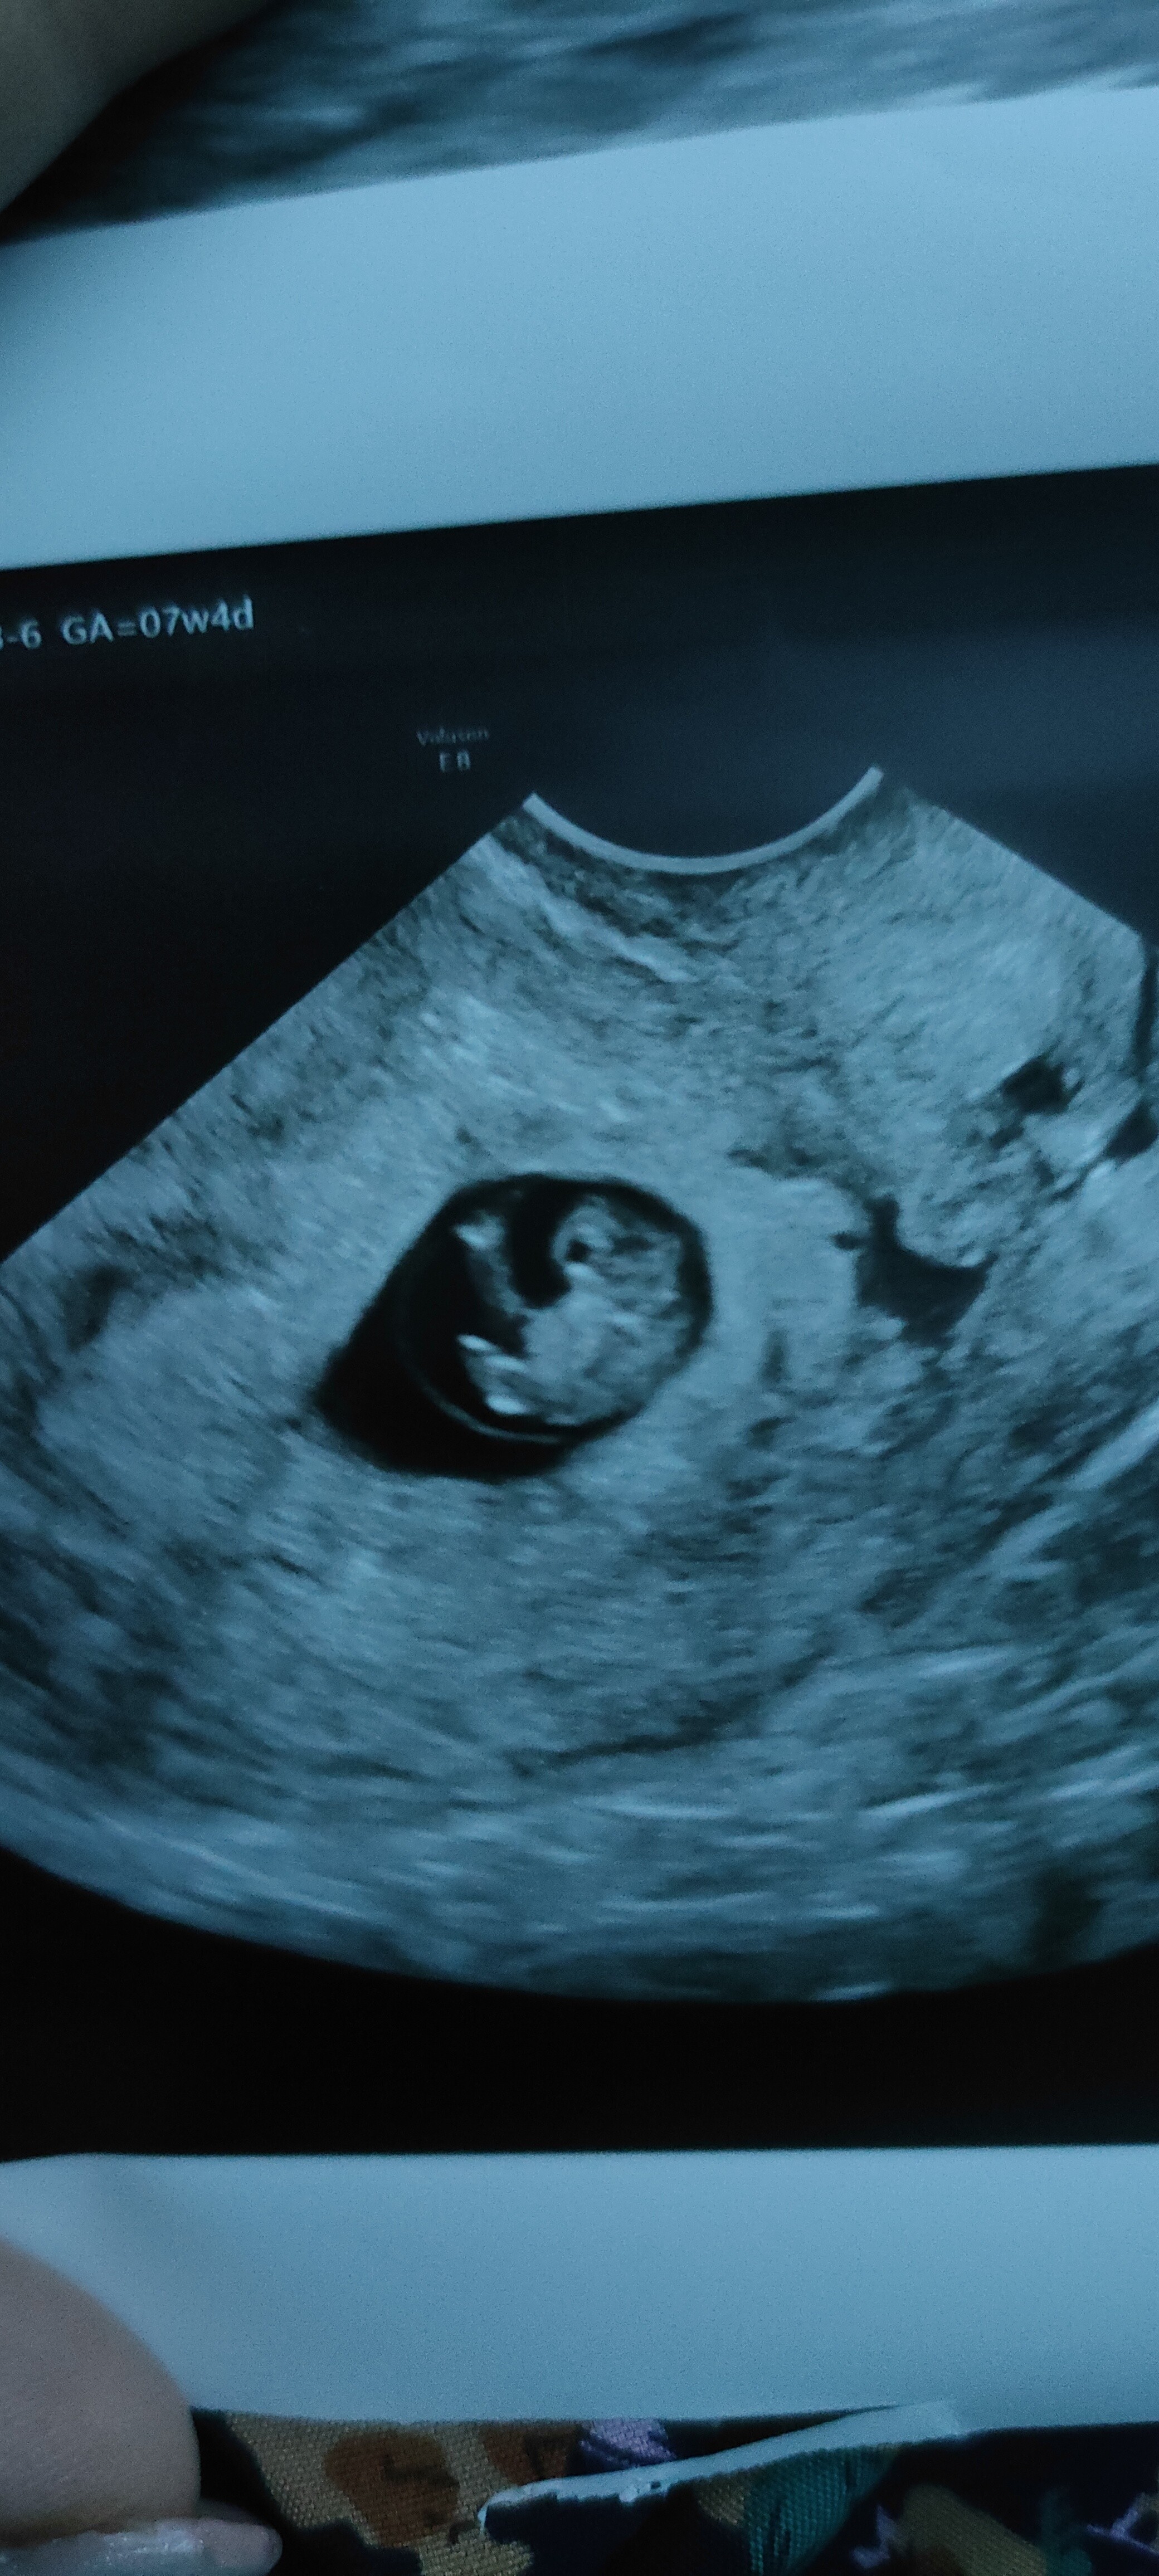

Tez byłam zdziwiona, ale doktor z dumą się pochwalił, że mają nowe, super USG i że już takie rzeczy można obserwować. Tutaj fajnie widać. Na tej focie. Po lewej stronie widać pępowinę. Do góry głowa z zaczątkami oczu, brzuszek, na dole zaczątki nóg . Na środku dziecka to ciemniejsze to rączki.